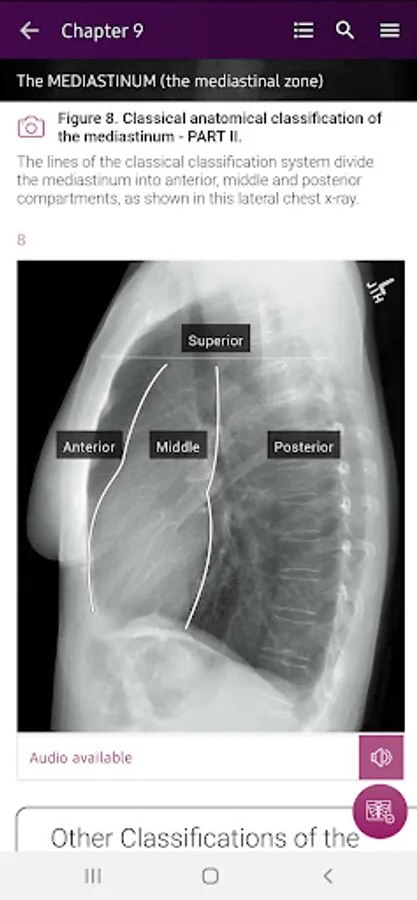

Section II* introduces the concept of radiological zones to give you a starting point in the understanding of the radiological anatomy of the chest. The next chapters review in detail the radiological anatomy of specific anatomical structures, also provide examples of how the x-ray image can change due to pathology. The final chapter explains how the individual structures come together to form the radiological image.